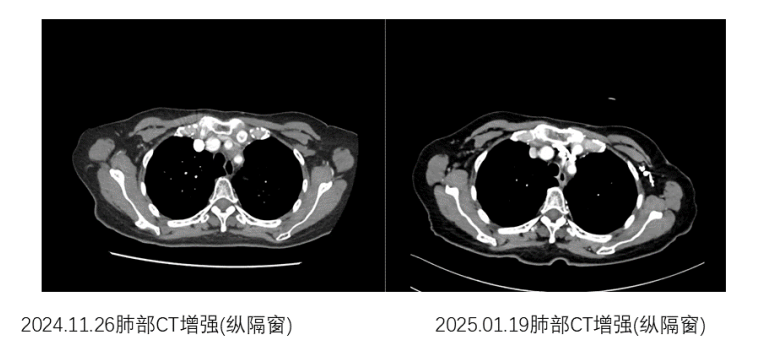

命运似乎不愿意放弃对常阿姨的考验:一年前,常阿姨的肺癌出现了缓慢进展,纵隔处淋巴结新发转移。梁淑静随后为常阿姨制定了高精度放射线疗法(IMRT,Intensity-Modulated Radiation Therapy)的治疗方案,即以高精度的放疗技术对肿瘤病灶实施精准打击。在16次放疗结束后,评估显示肿瘤显著缩小,后续采用靶向联合抗血管生成治疗维持,一直病情稳定。面对同年年底再次出现了胸廓入口处的纵隔淋巴结转移病灶较前缓慢进展,团队选择"靶向+放疗"组合拳,实现肿瘤再次退缩。

纵隔转移淋巴结治疗前后对比图